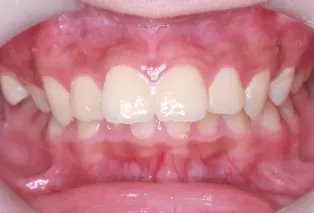

Photos intra-orales